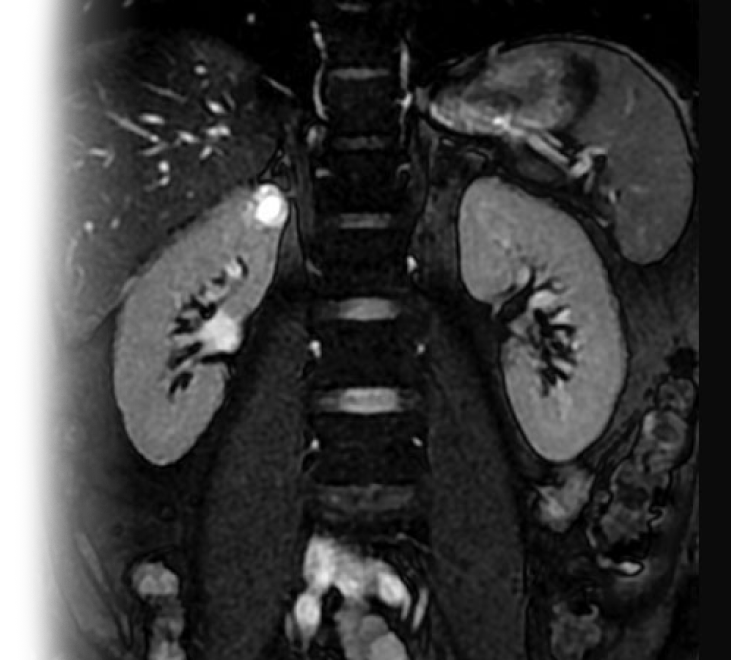

Магнитно-резонансная томография почек и надпочечников с контрастированием – важный метод исследования с введением контрастного вещества, который позволяет визуализировать обе почки, надпочечники, лоханки, верхние отделы мочеточников.

Как проводится МРТ почек и надпочечников с контрастом?

Перед укладкой в томограф необходимо снять все металлические предметы. Перед процедурой устанавливается внутривенный катетер для введения контрастного препарата непосредственно во время исследования. После этого пациент ложится на стол сканера, который постепенно перемещается в аппарат. Во время сканирования следует лежать неподвижно, чтобы получаемые изображения были четкими и неискаженными.